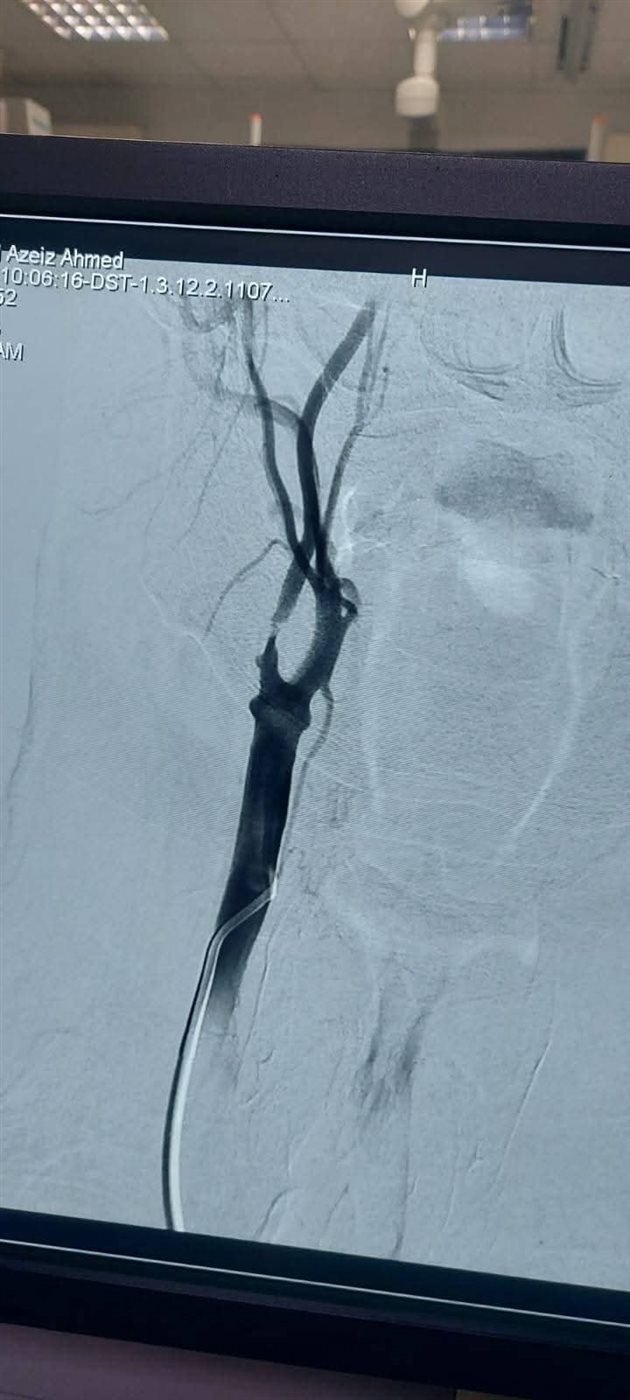

وكان المستشفى الرئيسى بجامعة أسيوط قد استقبل مريض يبلغ من العمر 65 عاما، يعانى من جلطات متعددة بالمخ نتيجة ضيق حرج بالشريان السباتي، وبعد إجراء الفحوصات اللازمة تقرر ضرورة التدخل بالقسطرة.

وتشكل الفريق الطبي من جامعة أسيوط الذي جاء برئاسة الدكتور مصطفى هاشم أستاذ الأشعة التشخيصية والتداخلية والقسطرة المخية، يعاونه الدكتور محمود رفعت مدرس واستشاري الأشعة التشخيصية والقسطرة المخية، والدكتور محمود نجيب مدرس واستشاري الأعصاب والقسطرة المخية، والطبيب عبد الرحمن عمر مدرس مساعد الأشعة التشخيصية والتداخلية.

وتعد القسطرة المخية واحدة من أهم التطورات الطبية الحديثة في تشخيص وعلاج أمراض الدماغ والأوعية الدموية، حيث تستهدف هذه التقنية المتقدمة علاج حالات مثل تمدد الأوعية الدموية والجلطات الدماغية، وتقدم بديلا آمنا وفعالا للجراحة التقليدية، كما تتميز بقدرتها على تقديم صور دقيقة للأوعية الدموية، مما يسهل التشخيص والعلاج في إجراء واحد.